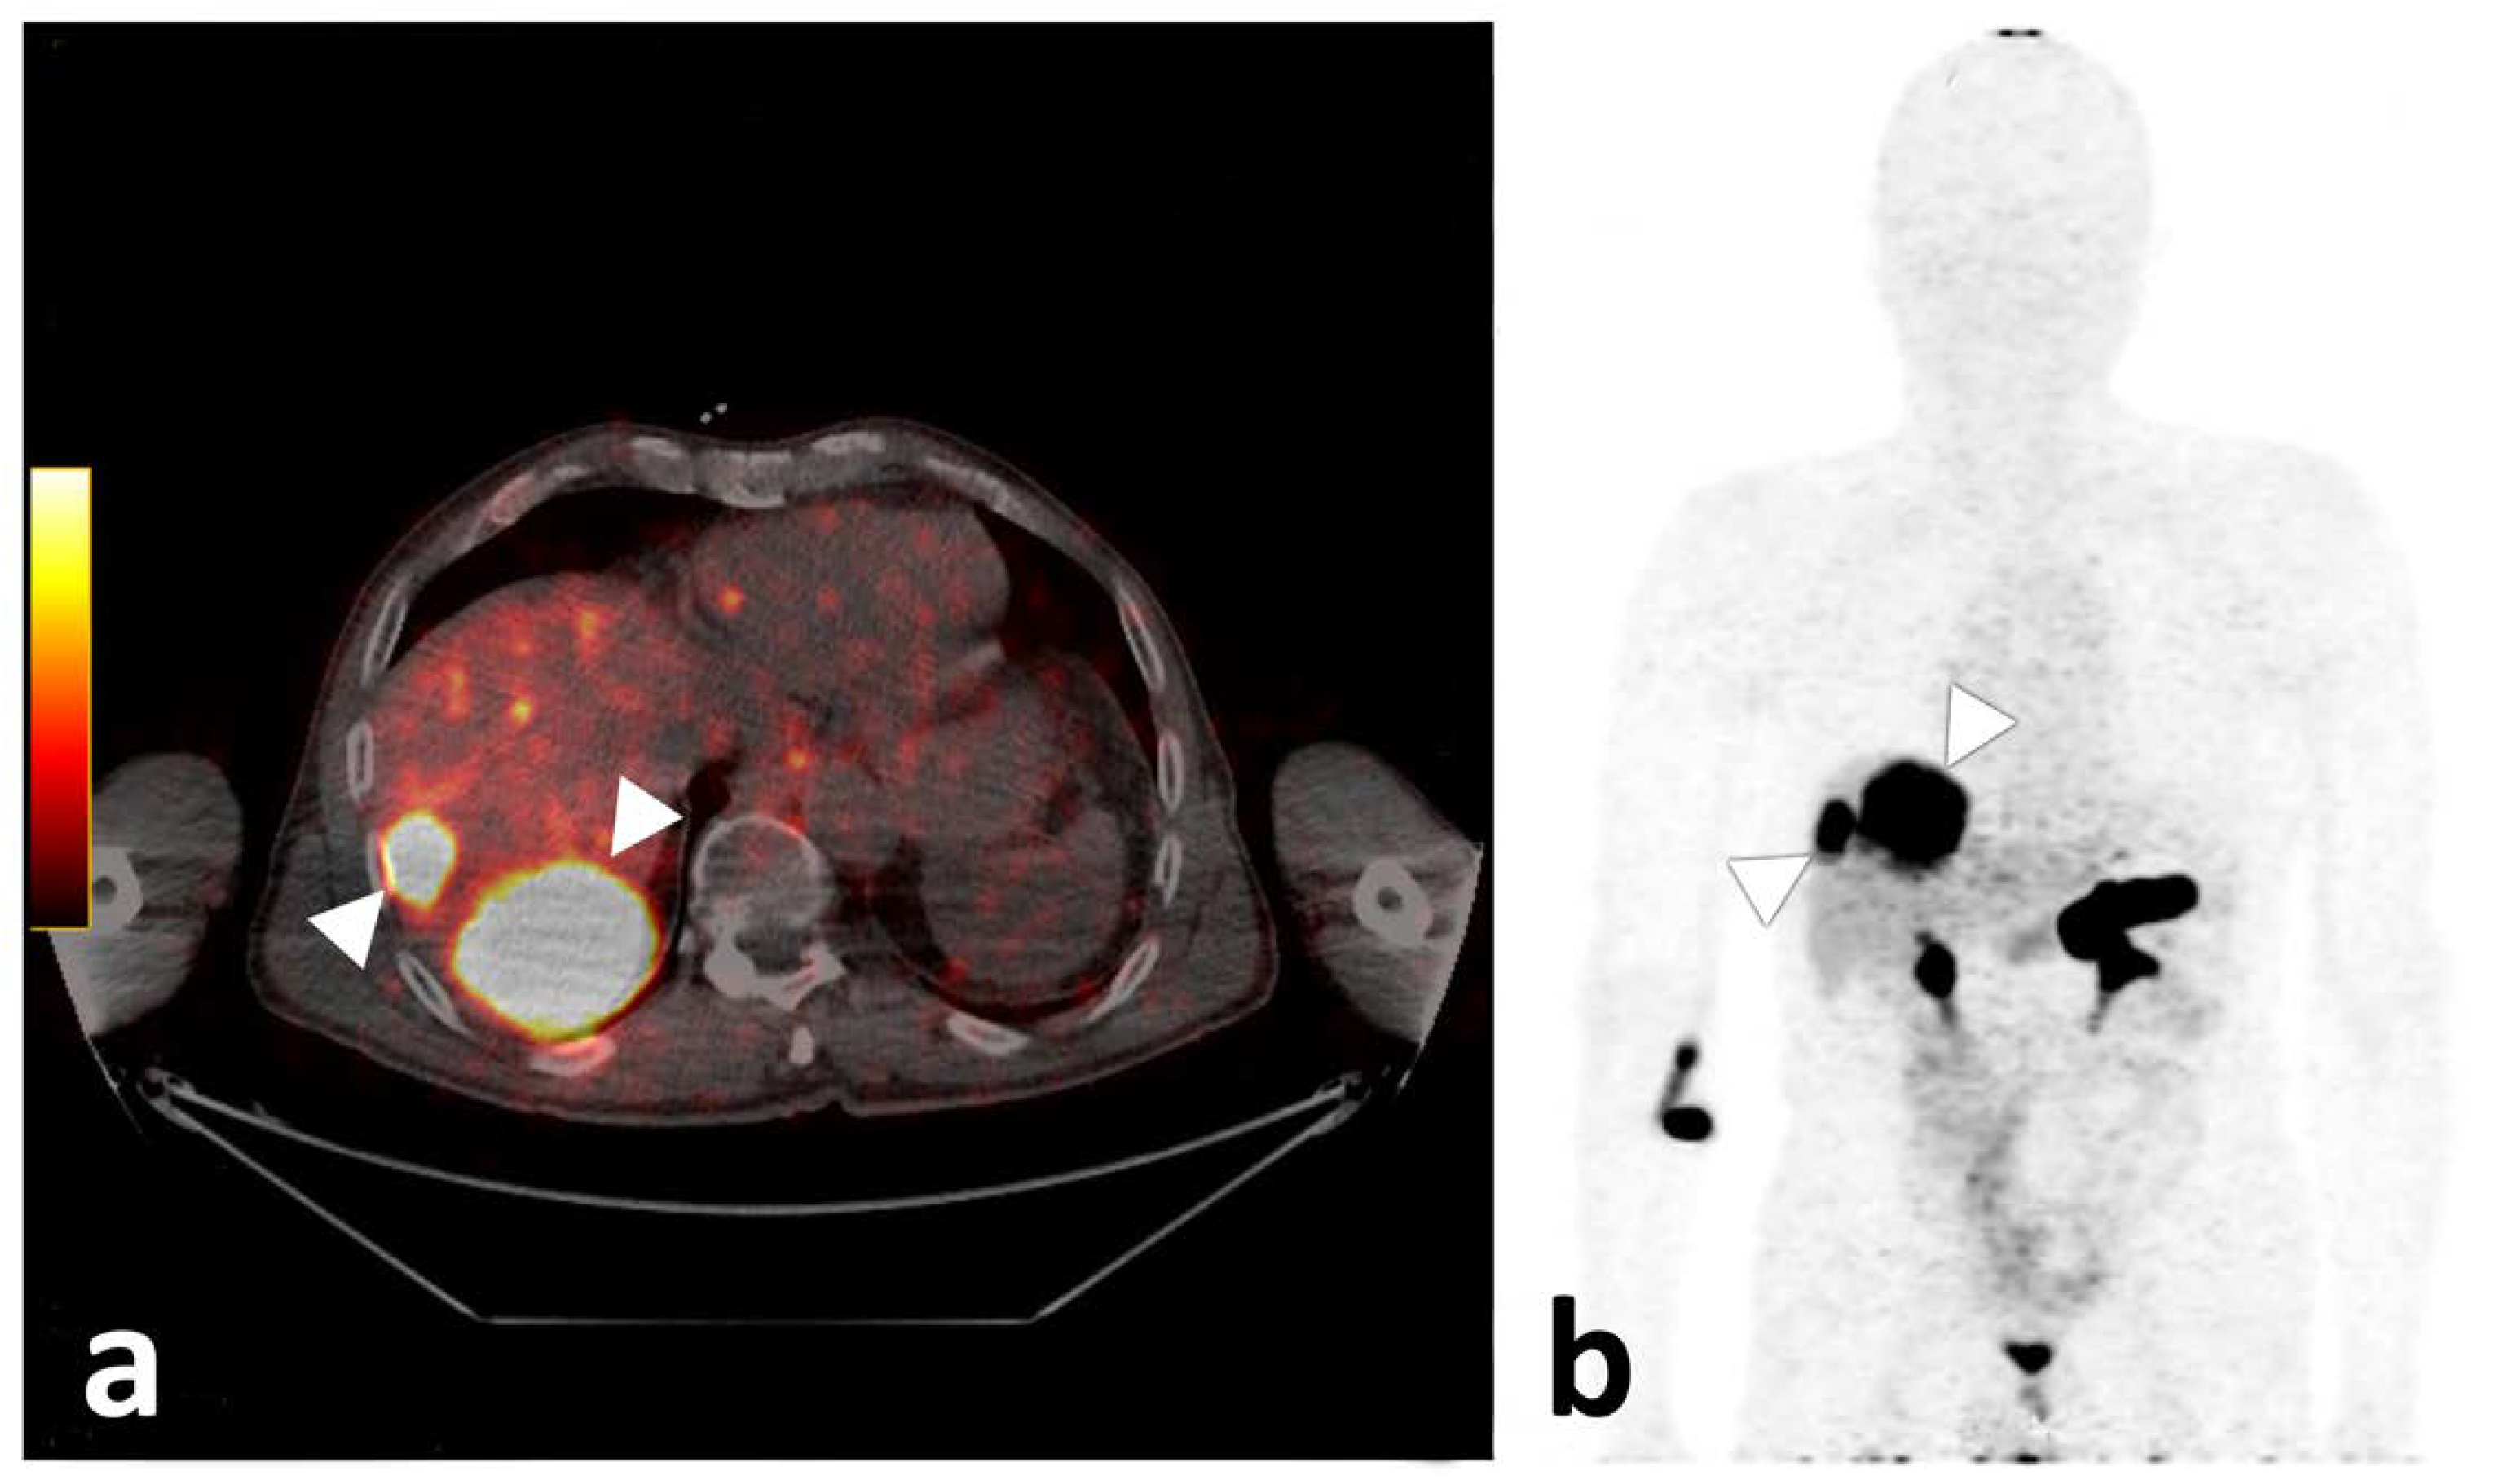

Even though physiological 68Ga-NeoBOMB1 organ distribution was uniform in all participants with strong uptake mainly in the pancreas and urinary system [25], tumor uptake varied. Tracer accumulation in all lesions was shown in 33.3% (n = 3) of participants: 33.3% (n = 3) showed tracer accumulation only in a subset of lesions; and 33.3% (n = 3) showed no increased uptake in tumor lesions identified on CT (please also refer to the illustrative Figure 5). In three participants, a mixed uptake—i.e., a subset of lesions with no tracer uptake in the presence of other lesions with tracer uptake—were observed (Figure 6). On a per-lesion basis, 17 of 37 lesions (45.9%) were detected by 68Ga-NeoBOMB1, whereas 16 lesions (54.1%) were negative on 68Ga-NeoBOMB1 PET, explained in part by a significantly lower tracer uptake in lesions with necrotic CT appearance. On the other hand, five lesions (13.5%) could only be identified via 68Ga-NeoBOMB1-PET and were not initially evident on CT. Although the current gold standard for staging GIST is still contrast-based CT including Choi-criteria to report on vitality [26], the decision was made early on to include all GIST lesions found with either CT, 68Ga-NeoBOMB1-PET, or a combination of both methods to define the overall disease burden most accurately. Overall, we could corroborate study findings by Dimitrakopoulou-Strauss et al. in patients with GIST using 68Ga-BZH3, that also showed variable uptake in only seven out of 17 patients and eight out of 30 lesions [14].

Figure 5.

Axial fused PET/CT image of participant 3, demonstrating two liver metastases with high tracer uptake (a). On the (b), the corresponding maximum intensity projection is given, also demonstrating strong physiologic pancreatic as well as rectal and diffuse small bowel tracer accumulation.

Figure 6.

Computed tomography (CT) with inserted magnifications (left) and axial fused PET/CT images (right) of participant 9, demonstrating lack of uptake of 68Ga-NeoBOMB1 in a mildly enhancing liver metastasis (white arrow, (a,b)) and two omental metastases with significant tracer uptake (c,d) [white arrowhead] and (e,f) [black arrowhead]). The latter lesion was missed upon initial staging by CT.